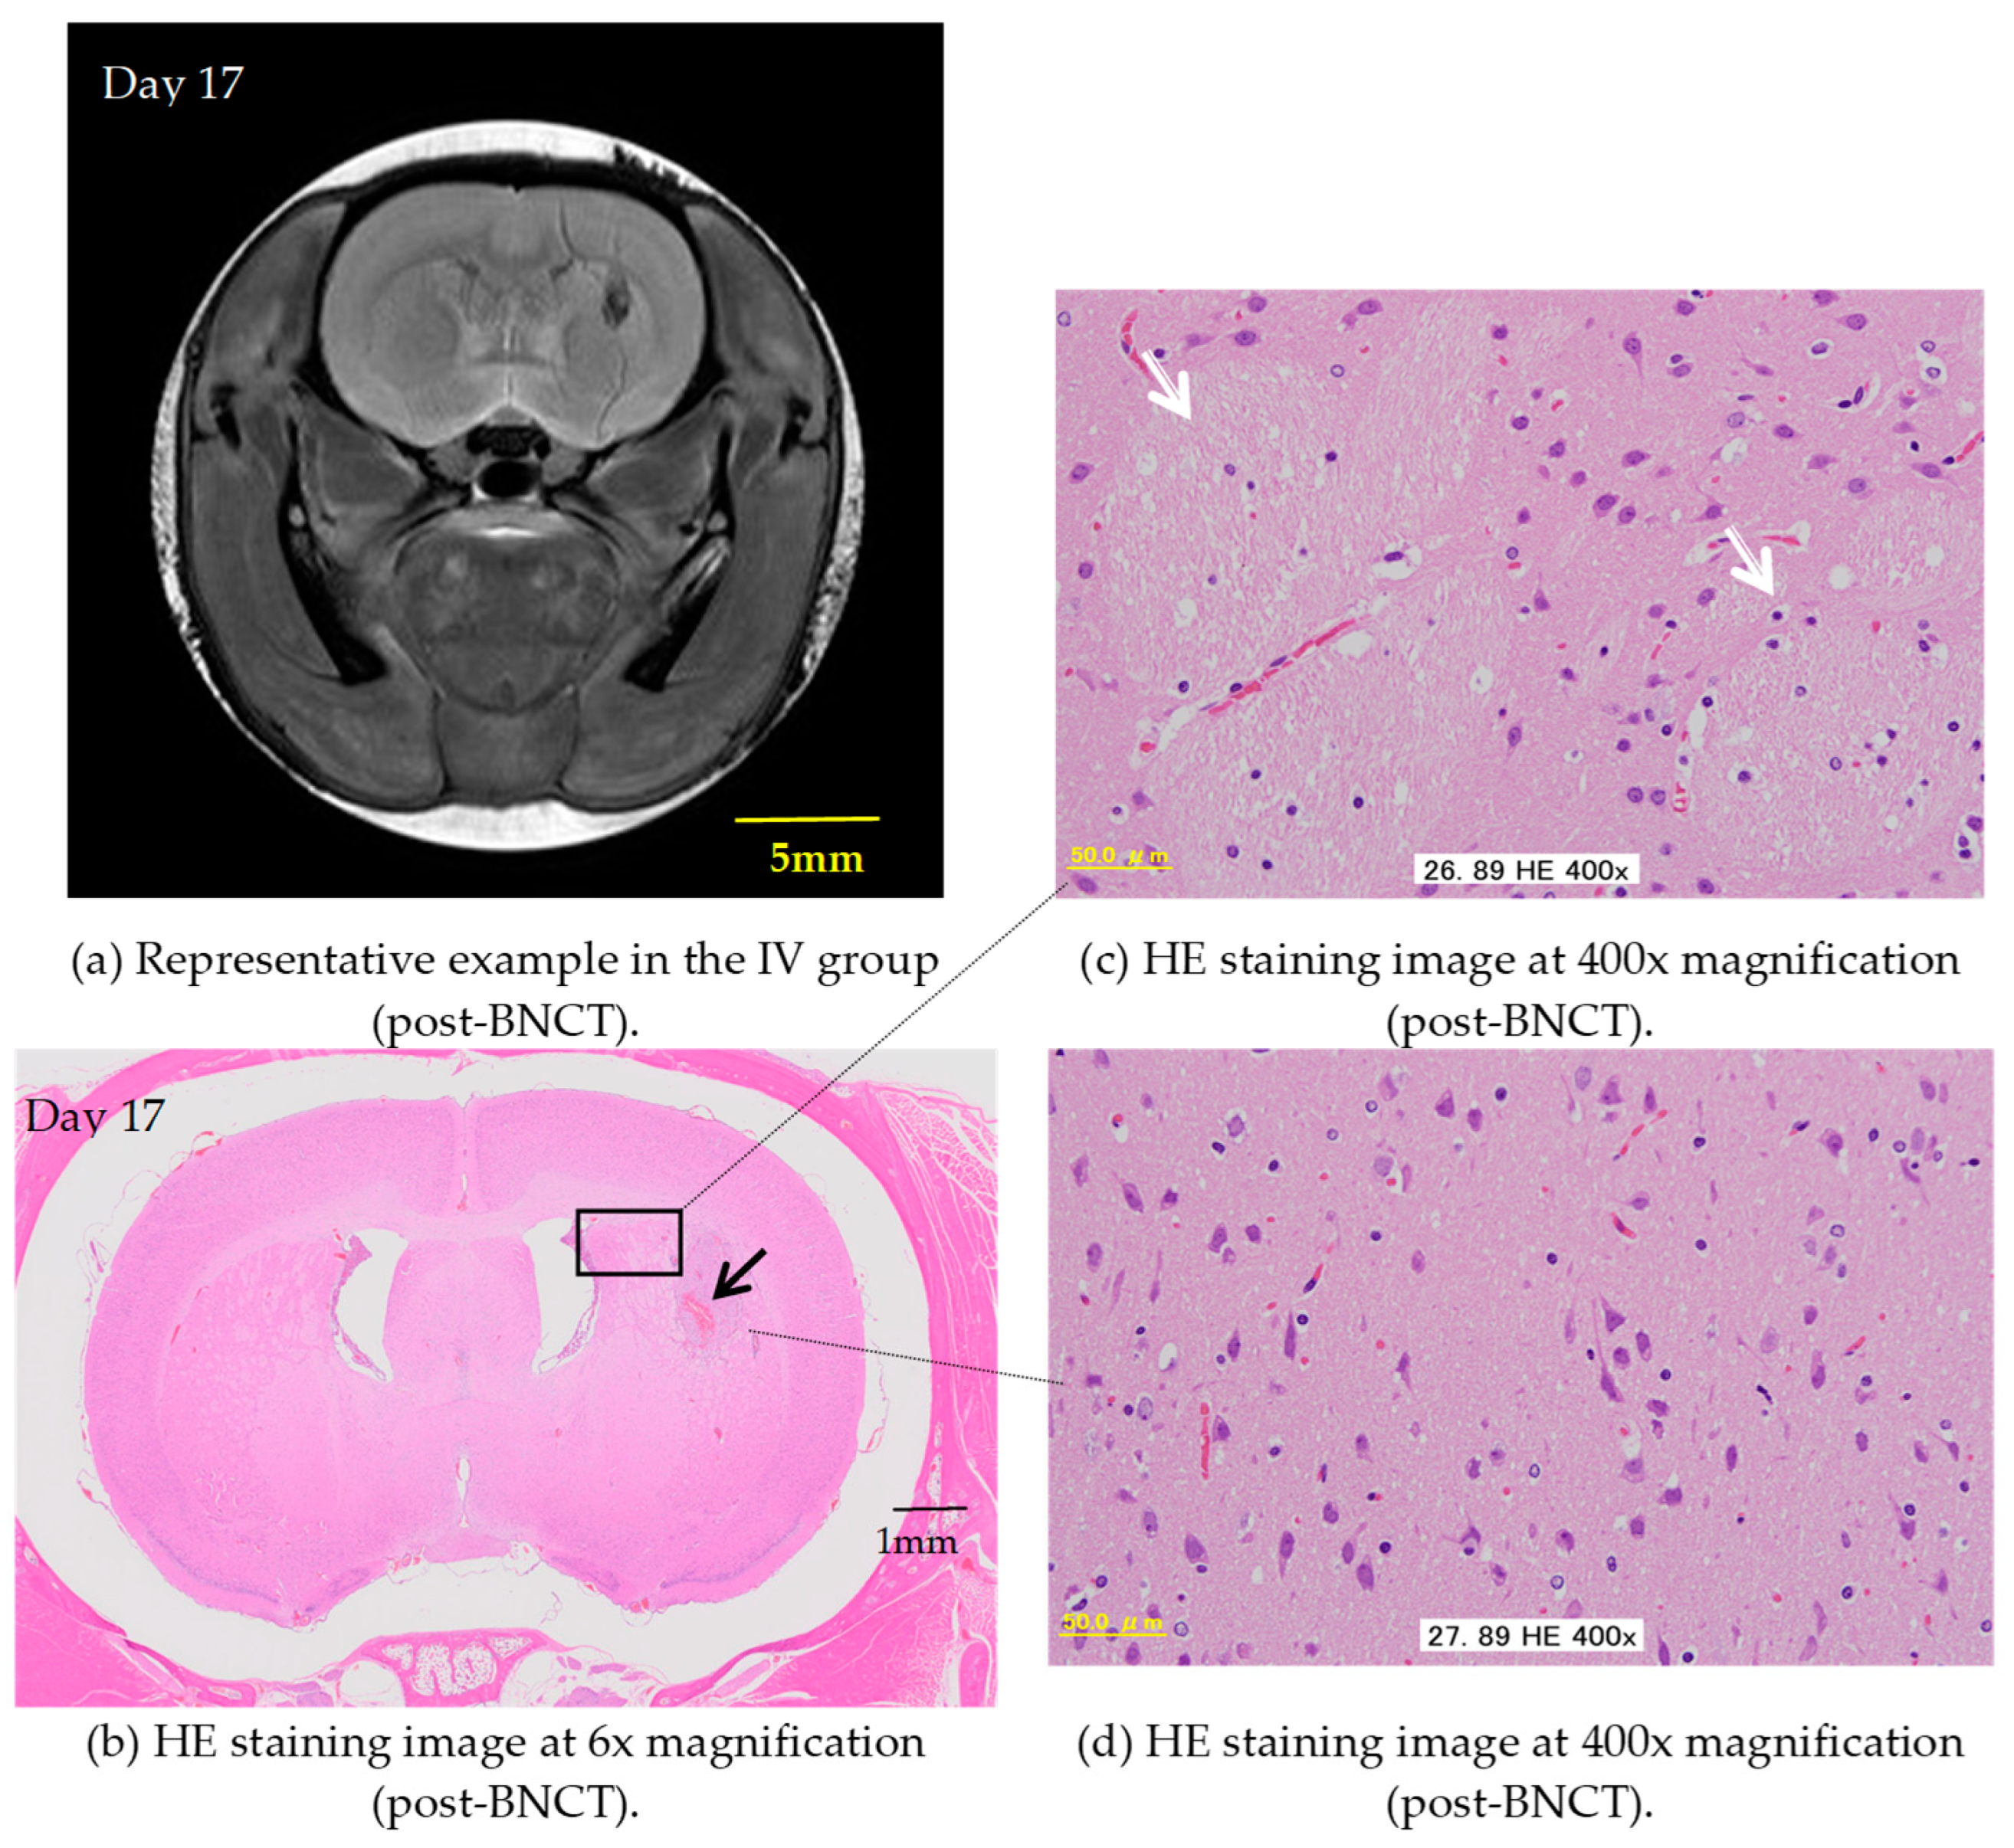

In the present study, some rats exhibit not only inhibited tumor growth but also a significant reduction in tumor volume as early as one week after BNCT with the IV BPA administration, highlighting the notable effectiveness of this therapy in rat models. Figure 4 demonstrates the remarkable histologically normal tissue levels post-treatment. When comparing the two administration methods, based on pathological examination, the IV method with a BPA dose of 350 mg/kg demonstrates better performance over the CSF method with a dose of 8 mg/kg/h (total 16 mg/kg), albeit only slightly.

Figure 4.

The figures represent an example of the IV group. (a) T2WIs after BNCT. (b–d) Show thin sections of rat brain tissue stained with HE depicting the brain’s condition after BNCT with the IV administration of BPA. (b) Shows 6× magnification under a microscope. Some hemorrhaging (⟶) is observed in the striatal area, but there is minimal evidence of inflammatory cell infiltration. (c) Shows 400× magnification under a microscope (the area enclosed by the rectangle in Figure (b)). The image indicates that the fiber bundles in the cerebral cortex near the hemorrhagic lesion (⇨) are at normal levels. (d) Shows 400× magnification under a microscope. Unlike the other samples, no signs of demyelination are observed in this specimen.